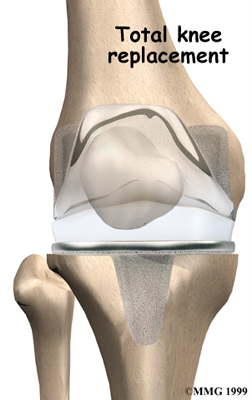

Artificial Knee Replacement

An artificial knee replacement is the ultimate solution for advanced knee OA.

Surgeons prefer not to put a new knee joint in patients younger than 60. This is because younger patients are generally more active and might put too much stress on the joint, causing it to loosen or even crack. A revision surgery to replace a damaged prosthesis is harder to do, has more possible complications, and is usually less successful than a first-time joint replacement surgery.

Related Document: FYZICAL Travelers Rest's Guide to Artificial Joint Replacement of the Knee